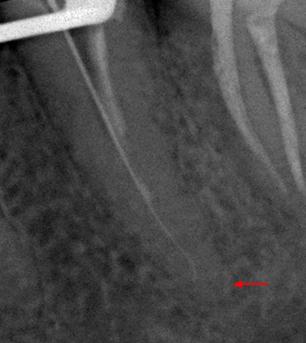

Пациент 45 лет направлен лечащим доктором на перелечивание 35 зуба.

Со слов пациента эндодонтическое лечение проводилось три года назад.

На рентгенологических снимках представлена картина до лечения, диагностический снимок и конечный результат.